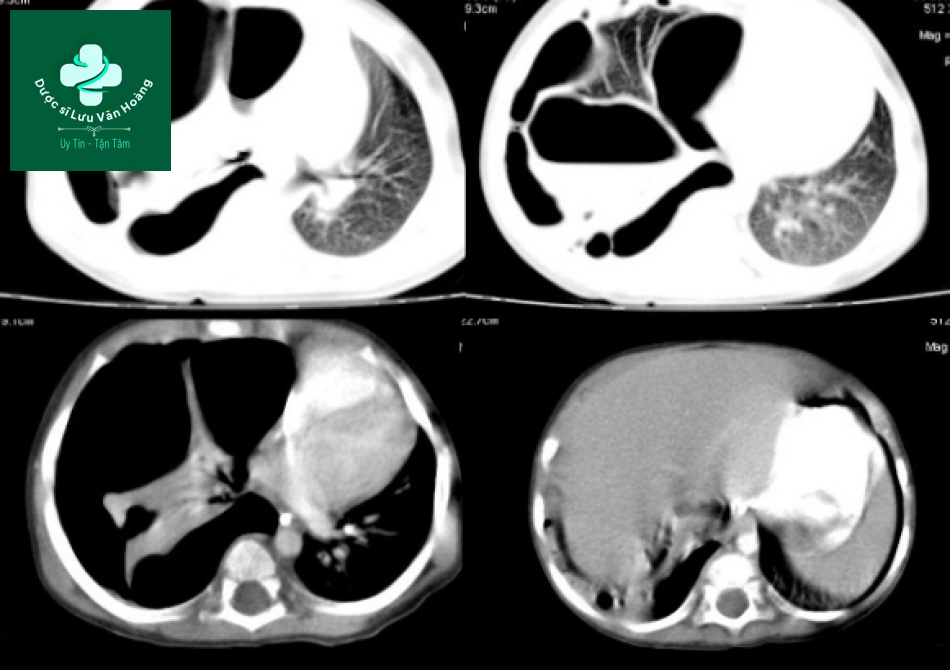

Case 2: CPAM type I.

Trẻ sơ sinh, suy hô hấp.

Phim x-quang cho thấy nhiều tổn thương dạng nang ở bên ngực phải, đè đẩy trung thất sang trái.

Trên CT: tổn thương dạng nhiều nang lớn ở trung tâm của thùy dưới phổi phải, xung quanh dày thành và thâm nhiễm không rõ ràng, có thể do viêm. Phân thùy đáy giữa và đáy bên tăng thể tích do thở bù, phân thùy đáy trước bình thường. Tổn thương gây hiệu ứng khối đẩy rốn phổi và thùy giữa ra phía trước. Phổi trái bình thường.